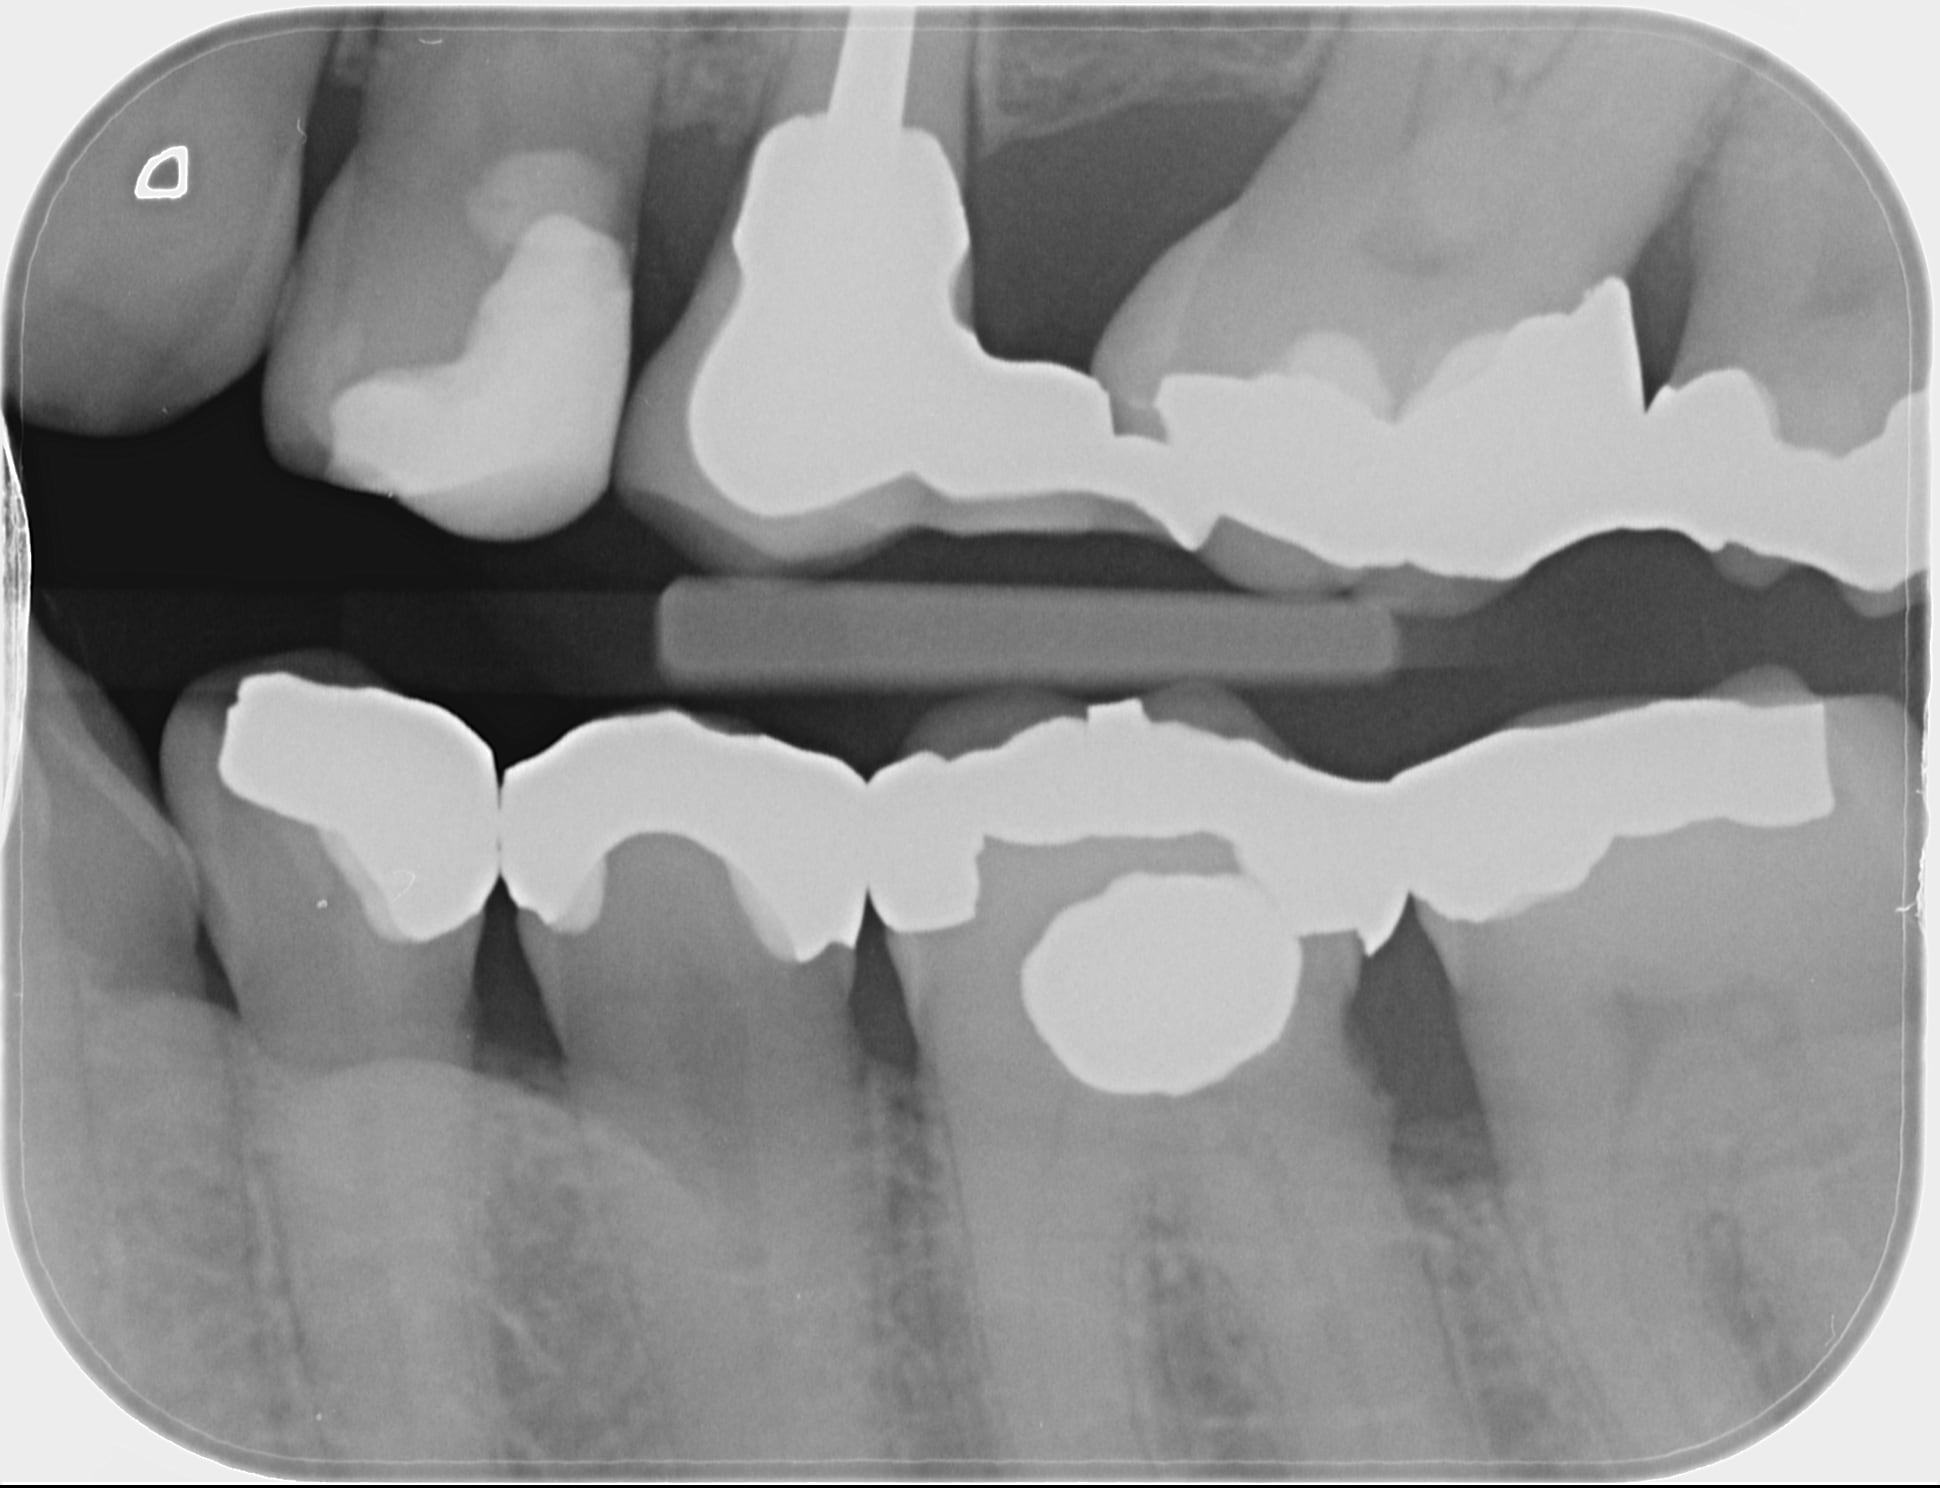

Quoi faire pour la 36?

couronne ou onlay effectivement, en fonction de la perte de substance.

Si pas possible de diguer, onlay metal.

Note qu'on pourrait se demander si un surfaçage ne serait pas suffisant. Y'a pas le bonhomme autour sur ta radio.

En vestibulaire , c 'est un amalgame ?

Oui transformé en composite le jour de l'empreinte.

Heureusement que c'est le désert en antagoniste ,

Parce les cuspides d'appui sont fragilisées .

C'est beau ces engins.

J'en ai démonté un y'a 3 semaines sur ma dentiste conseil, il devait avoir une trentaine d'années, fracture d'une paroi non recouverte.

Les 3 autres en bouche, datant de la même époque, n'avaient pas bougé d'un poil.

C'est vrai qu'en revoyant les photos j'aurais pu/dû faire un recouvrement cuspidien.